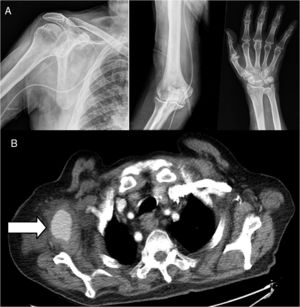

A male aged 83, receiving atrial fibrillation anticoagulation therapy with rivaxoaban, presented at the emergency department due to persistent pain his right shoulder which had spread to the back of his upper arm, forearm and wrist, of 10-day onset after an injury to the upper right limb in forced abduction. On examination a small throbbing axillary haematoma was observed, a strength of 1/5 on extending the fingers and of 3/5 on extending the wrist, hypesthesia in anatomical snuff box and first finger. Radial pulses were present and symmetrical. Requested X-rays showed no fractures or dislocations (Fig. 1a).

On suspicion of brachial plexus compromise cervical magnetic resonance imaging (MR) was requested, which resulted normal, together with electromyography which showed partial axonotmesis of the radial nerve. CT of the chest was also performed which showed an oval mass in the right armpit with irregular edges and a density similar to the axillary artery. As a result an angiography CTG scan was performed (Fig. 1b) which confirmed the said image was a continuity and pseudoaneurysm of the right axillary artery, axillary haematoma and axonotmesis of the ipsilateral radial nerve secondary to blunt trauma was diagnosed. The patient was referred for vascular surgery where a Doppler ultrasound scan was performed, draining of the haematoma and exclusion of the pseudoaneurysm through a stent. The patient is currently in physiotherapy treatment to recover strength lost from the injury and periodically goes to the outpatient rheumatology and vascular surgery department for check-ups.